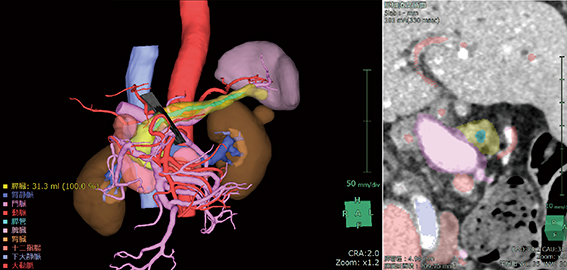

そこでわれわれは,REiLIの深層学習をベースに,従来の機械学習法を用いた技術では自動抽出が難しかった膵臓,膵管,膵臓周囲の動静脈,胃・十二指腸などの領域を,簡便に再現性良く抽出する技術を開発した(図1)。

図1 CT画像による膵臓三次元構築画像